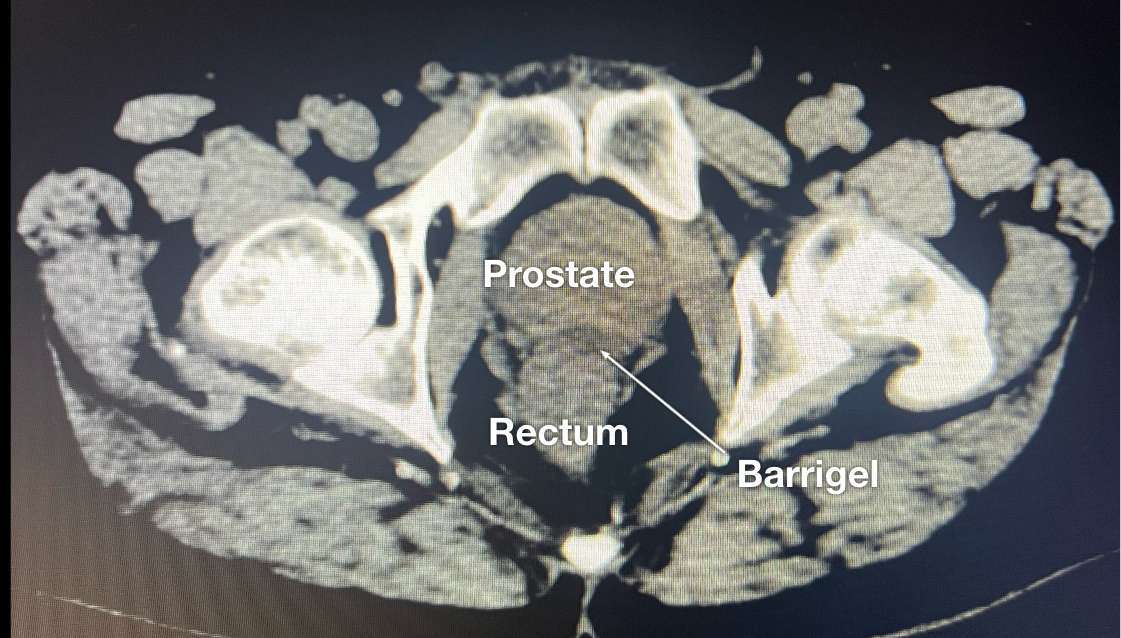

CT IMAGES

CT image courtesy of Escalarta López Ramírez, MD

Radiation Oncologist; Madrid, Spain